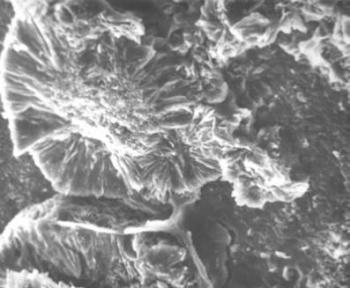

- Elektronmikroszkópos vizsgálatok